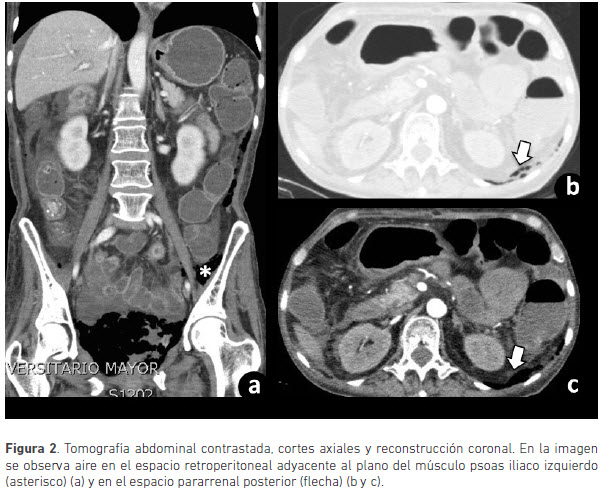

Debido a la enfermedad diarréica crónica se le realizó colonoscopia, en la cual se encontró pancolitis, así como una tomografía computarizada de abdomen en la que se evidenció aire en la pared vesical que se extendía a los tejidos blandos pélvicos y al retroperitoneo, compatible con cistitis enfisematosa (figuras 1 y 2).

Las alteraciones en la radiografía simple de abdomen incluyen un halo radiolúcido que delimita la pared vesical con o sin aire, en el área de proyección de la vejiga. La tomografía computarizada permite realizar el diagnóstico diferencial, logra una mayor caracterización de la distribución y extensión del aire. En ésta se identifican burbujas de aire en la pared vesical, el cual se puede extender al espacio perivesical, retroperitoneal, intraperitoneal y a tejido celular subcutáneo. Sólo se conoce de dos casos reportados con extensión del aire al espacio retroperitoneal (1,2).